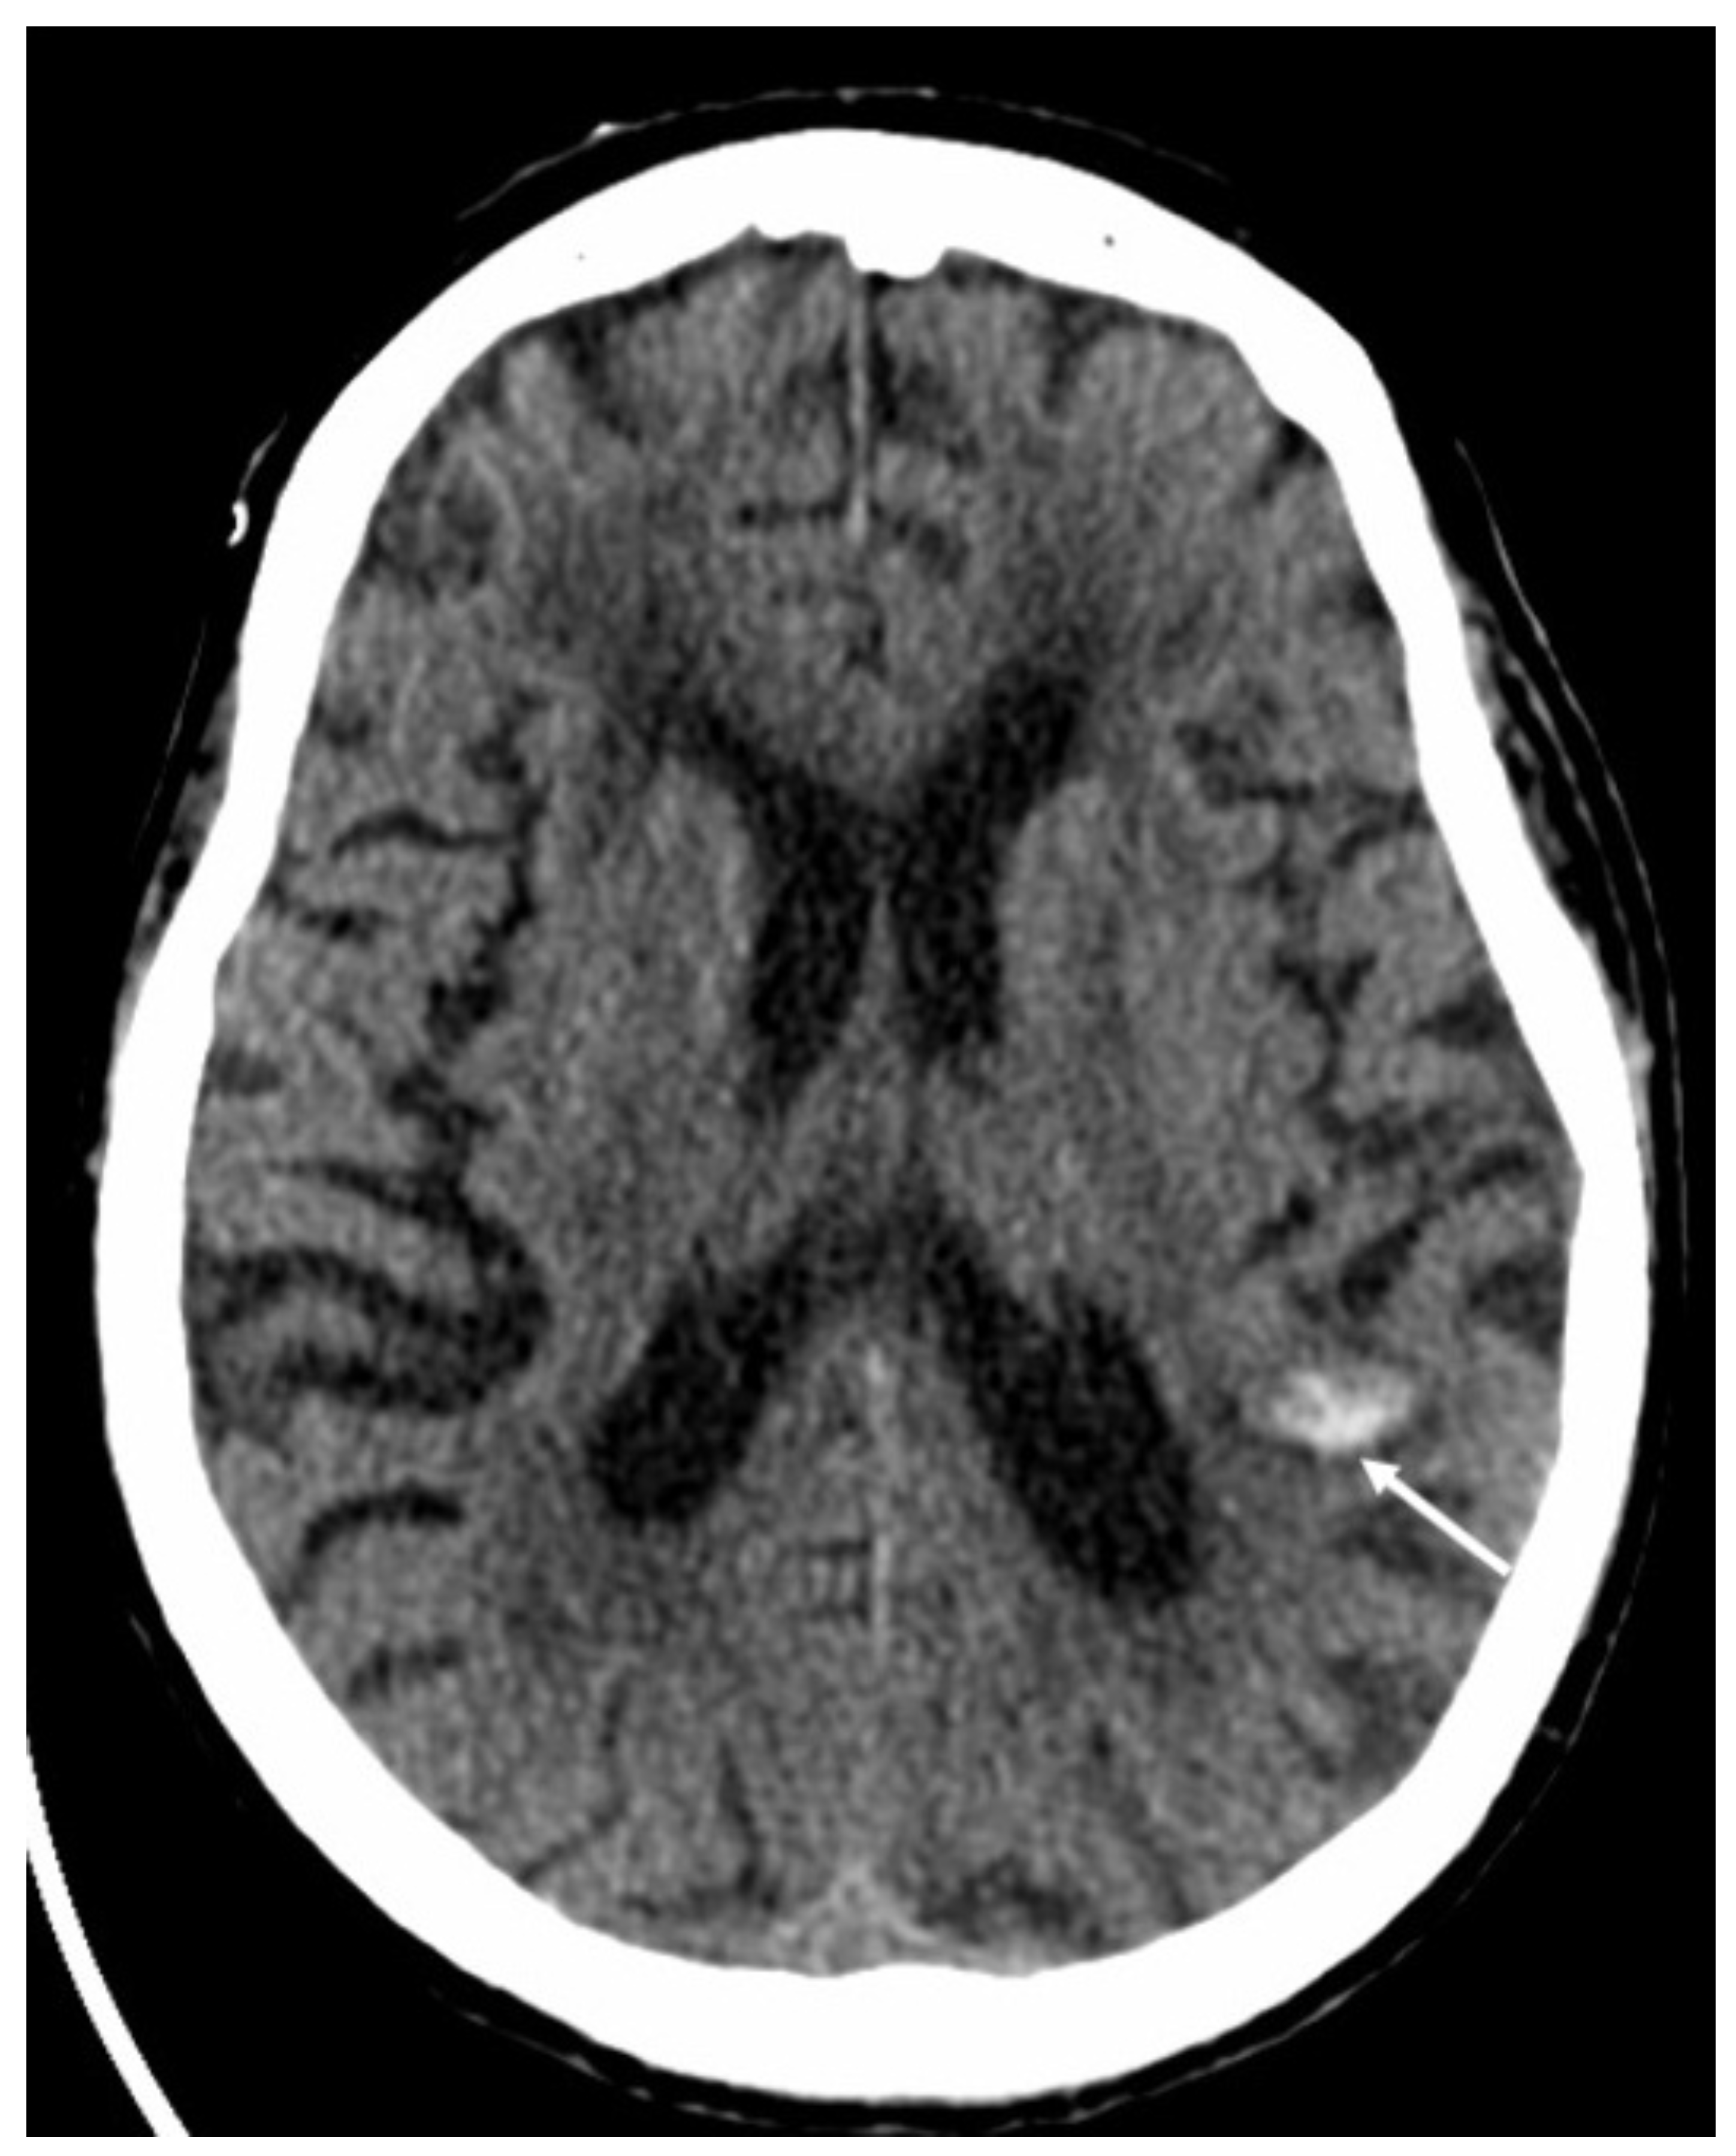

| Herpes Virus type 1 | • Mesio-temporal involvement • Bilateral and asymmetric pattern • Cortical hyperintensity on T2 and FLAIR, with restricted diffusion (acute phase) and cortical enhancement (subacute phase) • Hemorrhagic foci |

5. Viral Meningitis and Encephalitis